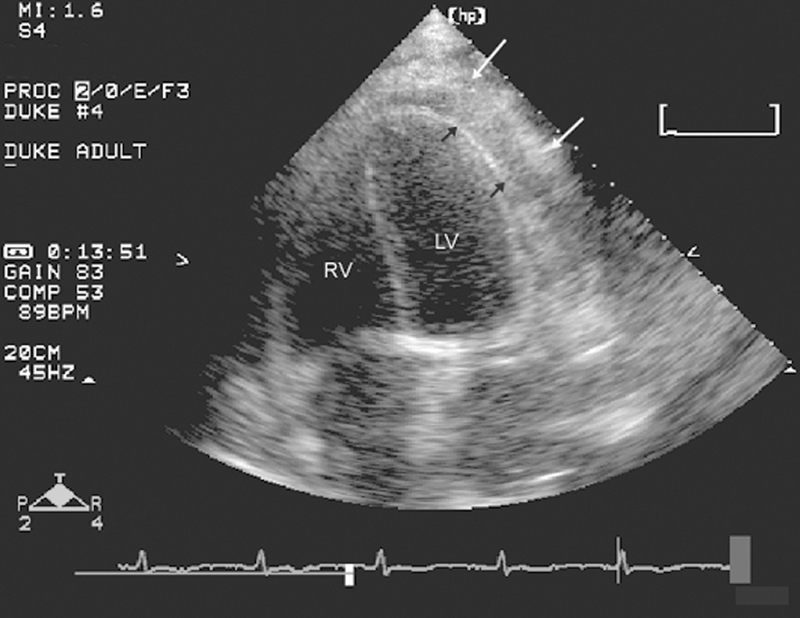

فحوصات تشخيصية لبعض امراض القلب والشرايين التاجية